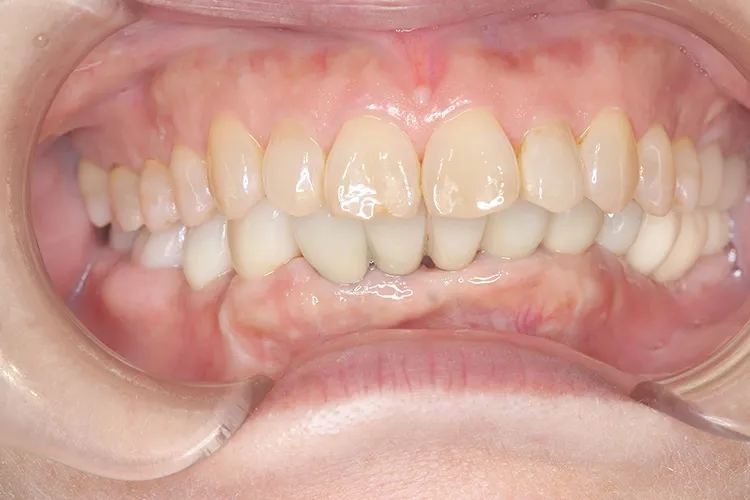

治療前

治療後

症例1/

臼歯2本

- 治療期間

- 10ヶ月

- 費用

- 90万円(税込)